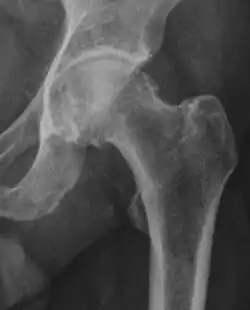

Projectional radiography ("X-ray") is often considered first line for FAI.[10] Anterior-posterior pelvis and a lateral image of the hip in question should be attained.[10] A 45-degree Dunn view is also recommended.[10][19]

| Measurement | Image | Target | Normal value |

|---|---|---|---|

| Center-edge angle of Wiberg | ![]() |

The superior-lateral coverage of the femoral head. | |

| Crossing ratio |

|

Percentage of acetabular walls crossing. Normal acetabulum is oriented in anteversion. Its value ranges from 15 to 20° in the equatorial plane of the acetabulum and decreases gradually towards the acetabular roof, where normal values range from 0 to 5°. Retroversion of the upper part of the acetabulum has been related with pincer type impingement. In radiography the presence of a "crossover sign" is produced when the posterior wall of the acetabulum crosses the anterior wall before reaching the acetabular roof. It is a sign of acetabular retroversion and it has been linked with overcoverage and pincer impingement. Nevertheless, this sign has been described in 6% of the normal population. Therefore, more important than its presence is the percentage of crossing. | <20%

| Alpha angle | ![]() |

Degree of bulging of the femoral head-neck junction: In normal conditions there is a symmetric concave contour at the junction of the femoral head and neck. Loss of this concavity or bone bulging may lead to cam type impingement. The degree of this deformity can be measured by the alpha angle. Although it can be measured in the cross-lateral view, the 45° Dunn view is considered more sensitive and the frog leg view more specific in determining pathologic values. |

| Femoral head-neck offset | ![]() |

Offset of the femoral head with regard to most prominent aspect of the femora neck | >10 mm |

| Offset percentage | Femoral head-neck offset related to femoral head diameter | >0.18

| |

| Tönnis angle |

Slope of the sourcil (the sclerotic weight-bearing portion of the acetabulum) | 0 to 10°

| Caput-sourcil angle[21] |

Superior to the Tönnis angle in cases without joint space narrowing or subluxation.[21] The medial point of the sourcil is at the same height as the most superior point of caput femoris. | −6 to 12°[21]